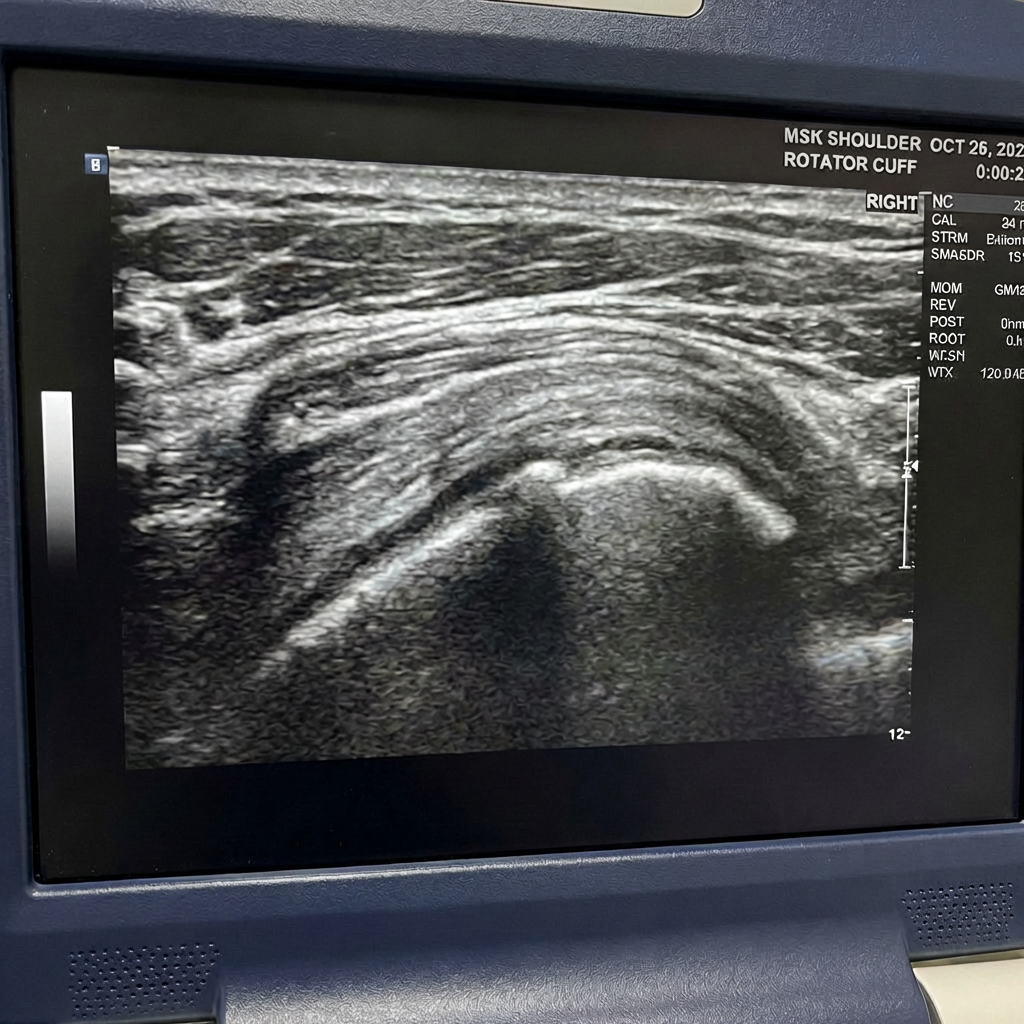

- Exames de imagem

Alguns exames podem confirmar o diagnóstico da lesão no manguito rotador, como:

- Ultrassonografia

- Ressonância magnética

- Raio-X

A ressonância magnética é considerada um dos exames mais precisos para avaliar o manguito rotador.